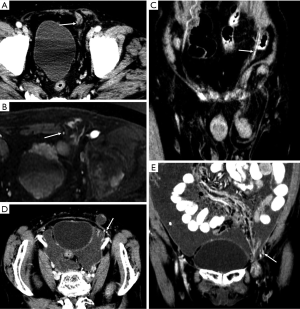

Hernias

Hernias are actually the most common “masses” in the abdominal wall, and unlike tumors or other tumor-like lesions, they may develop acute complications requiring emergent surgery. Common abdominal wall hernias include upper abdominal wall hernias, lateral abdominal wall hernias (also known as meniscuses), umbilical hernias, and inguinal hernias, with the latter being the most common. Inguinal hernias can be oblique or direct hernias. In oblique hernias, the hernial sac enters the scrotum from the inguinal canal outside the inferior abdominal artery. In direct hernias, the hernial sac protrudes from the “inguinal triangle” or “Hesselbach triangle” on the medial side of the inferior abdominal artery.

Although the clinical diagnosis of abdominal hernias is relatively easy, CT or MRI can help distinguish between abdominal hernias and abdominal or abdominal wall tumors by showing the herniation of fat or intestines through the fascial defect, in addition to complications of intestinal fistulas, such as ischemia and obstruction (59). As an interesting finding in our routine work, CT can be used to identify the inferior epigastric artery and can help distinguish oblique and direct hernias, which is important for surgery (Figure 12).

Hematomas

Anterior abdominal wall hematomas usually occur in the rectus abdominis muscle and result from damage, such as a trauma or surgical intervention, to the superior or inferior epigastric arteries or direct tearing of the rectus muscle. Other uncommon reasons are clotting deficiency or anticoagulant treatment. Hematomas in the absence of trauma or after light trauma are usually difficult to distinguish from tumors with hemorrhage in clinical practice, and contrast-enhanced MRI will facilitate the differential diagnosis (64).

Hematomas present as well-defined, hyperdense rectus masses on unenhanced CT and may show active contrast extravasation on enhanced CT. Their appearance on MRI depends on the stage of the hemorrhage. Deoxyhemoglobin in the acute stage manifests as iso- or hypointense areas on T1WI and T2WI. Methemoglobin in the subacute stage often produces high SI in the form of a peripheral rim, which is a very useful diagnostic factor (Figure 14). In the chronic phase, the dark hemosiderin rim on T1WI and T2WI is a useful discriminating feature (1). CT and MRI help achieve an accurate diagnosis and can be used to evaluate the extent of a hematoma and the presence of active bleeding (3).